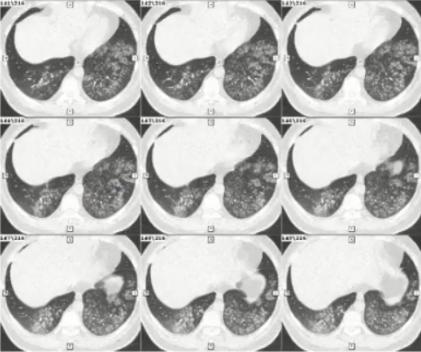

图1 患者的影像学以实变为主

病例1

女性,15岁,既往曾行脊柱侧弯矫形术。因发热、咳嗽、咳黄痰1周入院。

发病后2天起予头孢曲松+阿奇霉素治疗至入院当日,日最高体温从39.9℃降至38.3℃,但发热、咳嗽、咳黄痰无进一步好转。

血常规检测:

• 发热第3天:WBC 5.34×109/L,N 0.659,CRP 1.063mg/dl

• 发热第7天:WBC 4.07×109/L,N 0.691,CRP 1.547mg/dl

CK 357.5 U/L,LDH 277.1 U/L